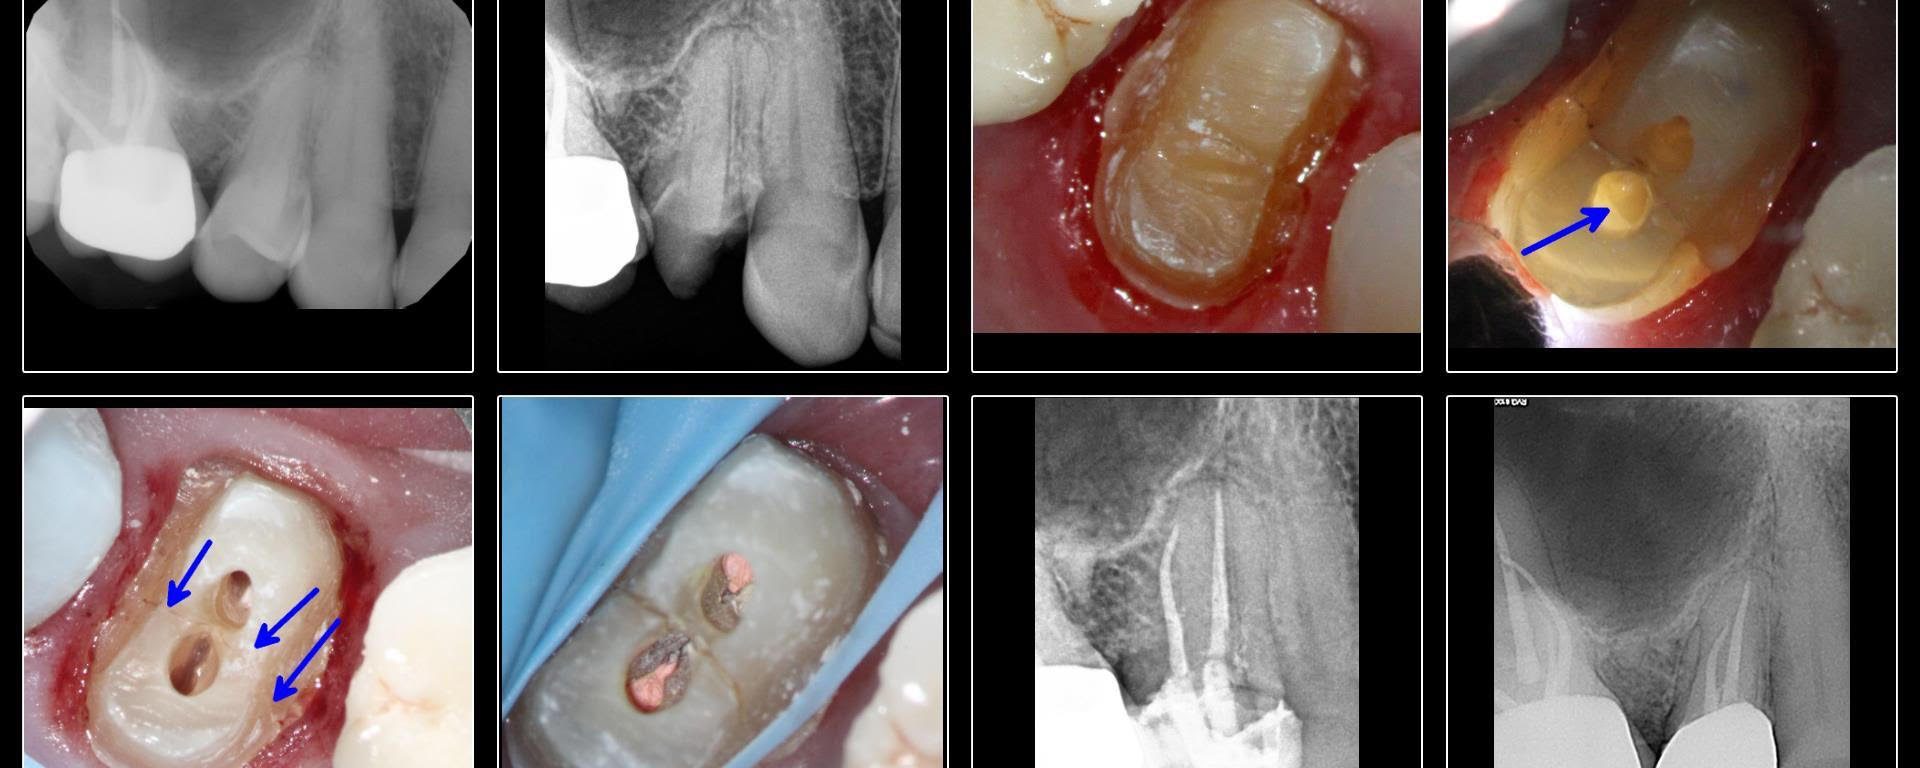

Fractured Bicuspid/MIE

July 3, 2018 3 comments

I wanted to post this interesting case. She is the sister of an endodontist colleague( no pressure) who arrived in my office with a temp crown and in severe pain. As soon as I took a look, I realized the tooth had a bad MD vertical fracture with no probings or mobility but would likely […]

MIE: Untreated pal canal

July 3, 2018 4 comments

White , 70 yo, male presented completely asymptomatic but with a buccal ST.  Tooth had a post and crown and patient did not want to have it removed.  CBCT  showed missed palatal canal. Access was done above the P cusp with the intention of locating and treating the missed canal only. Last PA is a […]